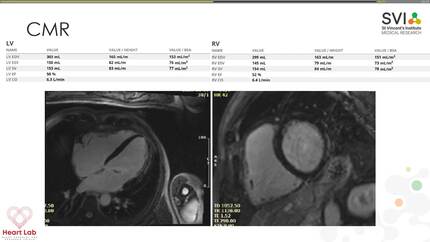

A challenging case of a professional football player with exercise-induced ventricular tachycardia